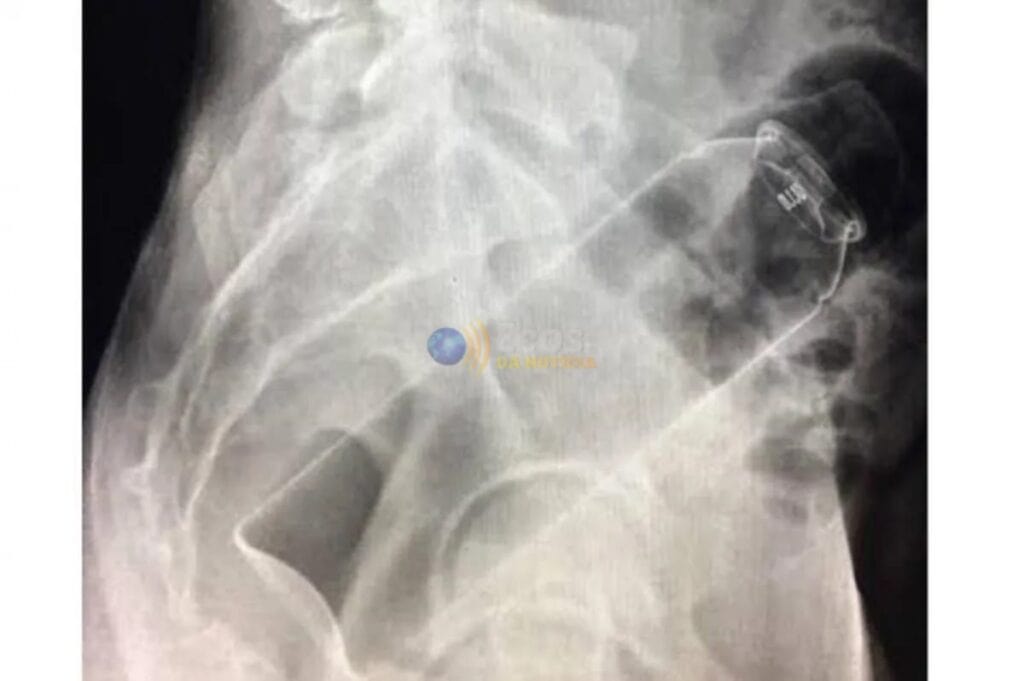

Um empresário viveu uma situação constrangedora na madrugada desta quinta-feira (13), após um frasco de desodorante ficar preso em seu reto. O caso inusitado ocorreu na cidade de Ji-Paraná, região Central de Rondônia.

Segundo informações apuradas, o homem teria introduzido o frasco no ânus por conta própria, mas o objeto acabou ficando preso, impossibilitando sua retirada. Desesperado, ele entrou em seu carro, um Volkswagen Virtus, e dirigiu até um hospital particular em busca de atendimento.

No local, a equipe médica realizou um procedimento para remover o desodorante, que foi concluído com sucesso. O empresário permaneceu em observação por algumas horas e recebeu alta ainda durante a madrugada, após avaliação dos profissionais de saúde.